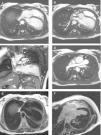

As the echocardiographic images were suboptimal, cardiac magnetic resonance imaging (MRI) was performed (Figure 3), confirming leftward displacement of the heart (Figure 3A) and hypermobility (Video 1). Absence of left ventricular pericardium and pericardial fat (Figure 3B and C) and interposition of lung tissue between the great vessels (Figure 3D) were also observed. This last finding is considered a specific diagnostic sign (for some authors even a pathognomonic sign) of congenital pericardial defect.

Figure 3.

Cardiac MRI images. (A-D) Steady-state free precession images. (A) Axial image showing left and posterior heart displacement. (B) Axial image displaying non-visualization of the pericardium and pericardial fat around the left ventricle (between the white arrows). (C) Coronal image showing absence of the pericardium and pericardial fat around the left ventricle and great vessels (between the white arrows), with lung tissue interposition in the several recesses where the pericardium is usually found. (D) Axial image showing lung tissue in the aorto-pulmonary window (white arrow), which is considered a pathognomonic sign of this condition. (E) T1-weighted axial image with no abnormalities, particularly, fat tissue deposition. (F) Delayed gadolinium-enhanced axial image with no macroscopic areas of myocardial fibrosis/necrosis.